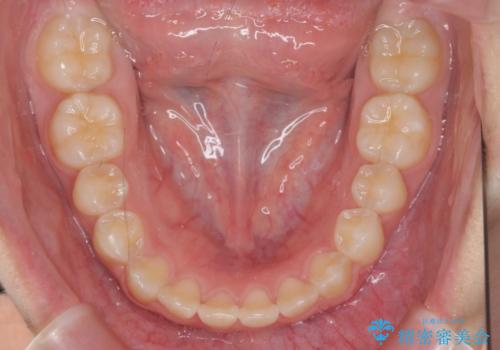

インビザラインで行う八重歯の治療

- 笑った時に目立つ八重歯の矯正治療を求めて来院されました。

マイクロインプラントを用いた臼歯の後方牽引、およびゴムかけ等の付加処置を駆使して八重歯の治療を行っていきます。

しっかりとゴムかけを頑張っていただいたおかげで、上顎臼歯の後方移動が達成されしっかりとした噛み合わせの構築と、八重歯の治療を達成することができました。